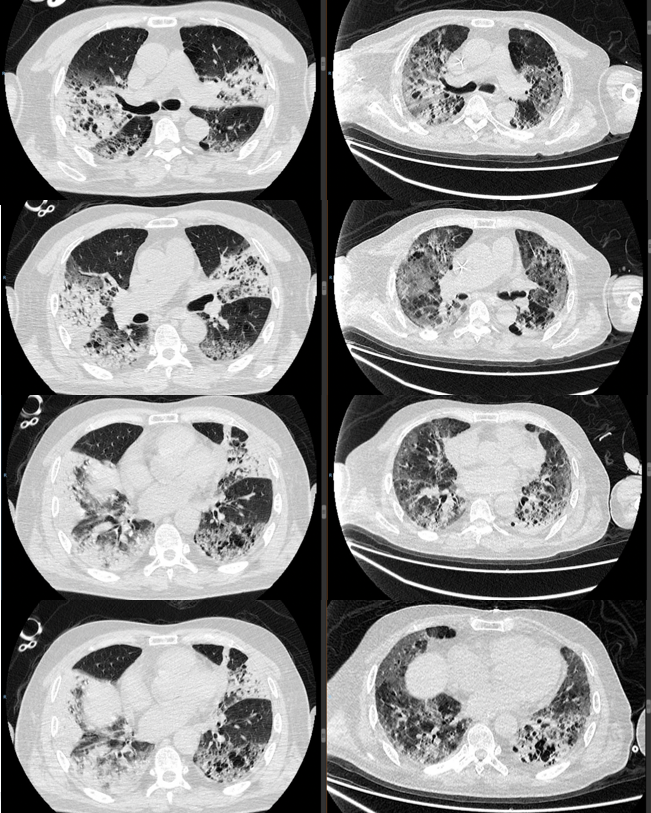

最终诊断机化性肺炎。采用激素冲击治疗(图2),3个月后患者肺部病灶明显吸收(图3)。2年后随访,患者情况较好。

图3  患者胸部CT